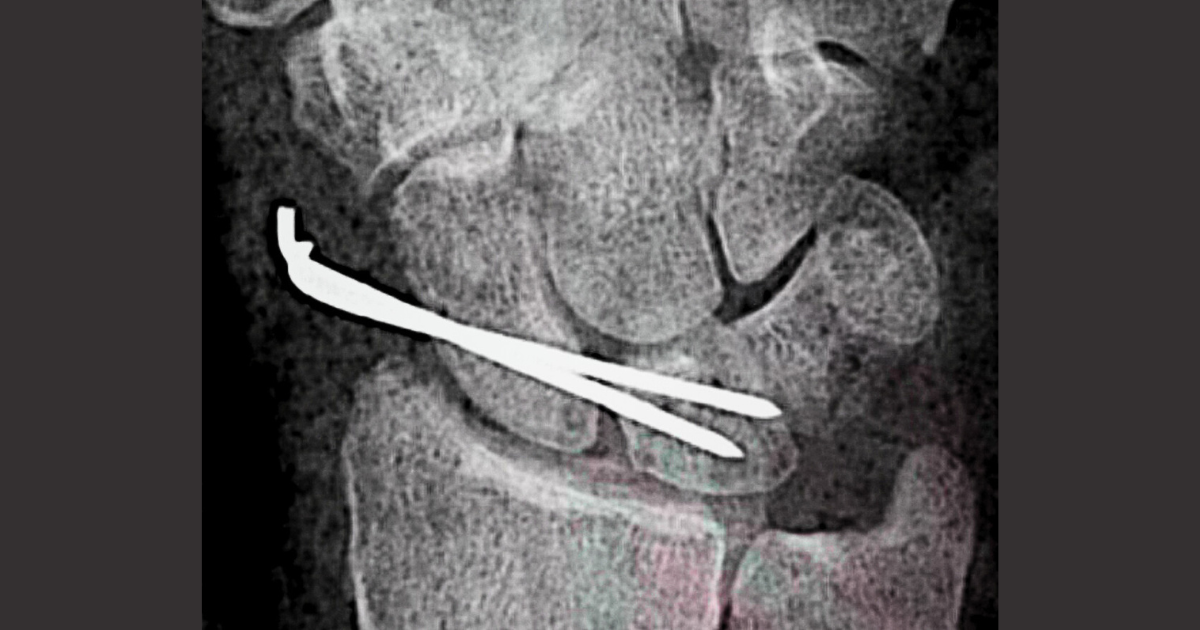

Artroscopia de muñeca

+2

#6. Dolor tras reparación artroscópica ligamento escafolunar.

Cómo distinguir dolor neuropático de el de adaptación mecánica.

#5. Ligamento escafosemilunar.  Cirugía abierta.

Decodificando la hoja quirúrgica.